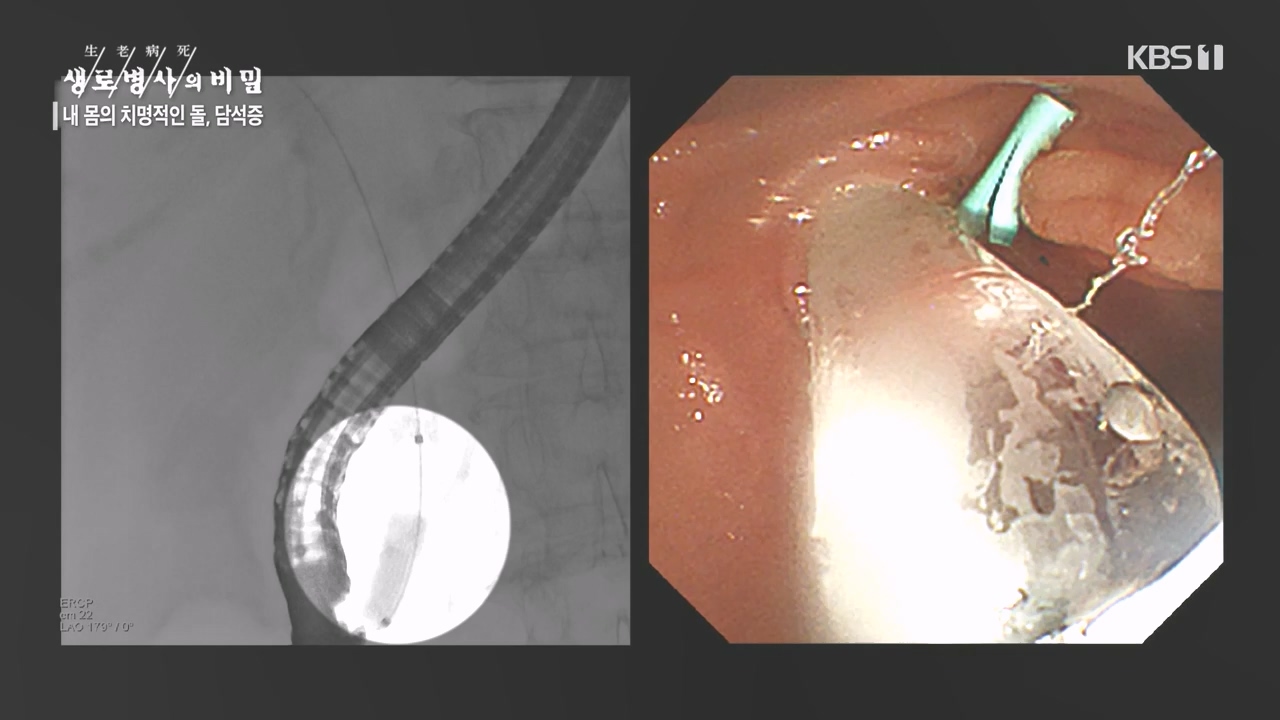

[박은철 기자] 담석증은 지방 소화를 돕는 담낭(쓸개)에 담즙이 굳어서 돌처럼 덩어리가 생기는 질환이다. 주로 쓸개주머니라 불리는 담낭 안이나...

내 몸의 치명적인 돌 담석증